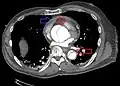

Follow-up

Closure of the lumen of a Type B aortic dissection following medical management

The long-term follow-up in individuals who survive aortic dissection involves strict blood pressure control. The relative risk of late rupture of an aortic aneurysm is 10 times higher in individuals who have uncontrolled hypertension, compared to individuals with a systolic pressure below 130 mmHg.